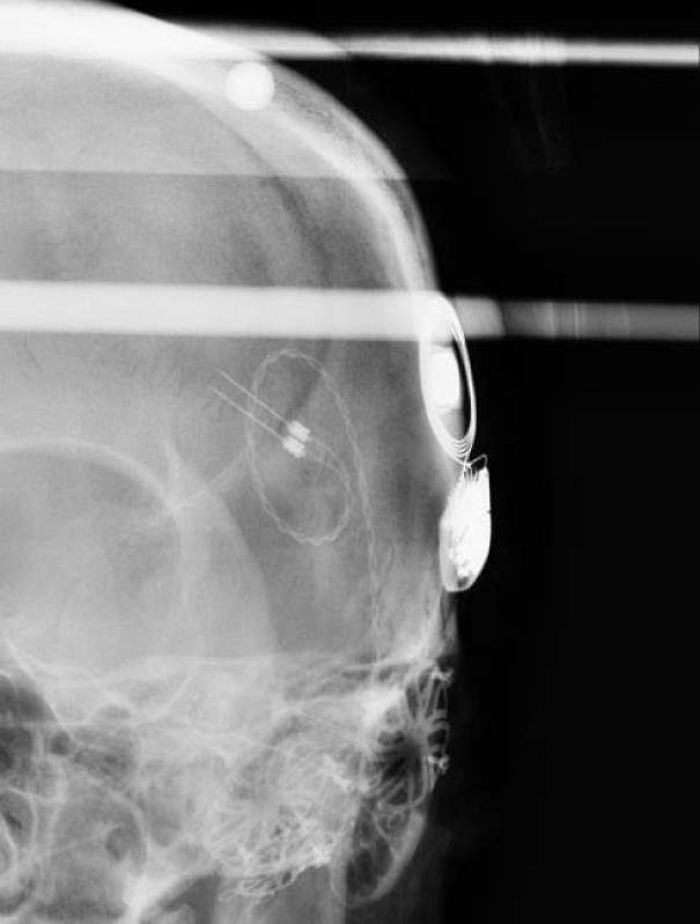

My Chest X-Ray After 3 Pacemaker Surgeries, A Median Sternotomy And Valve Repair

A Nice Clear X-Ray Showing My RNS Device, The Leads That Run To The Point Where My Seizures Originate

And also the brackets holding my skull together after my craniotomy (and the staples holding my scalp together).